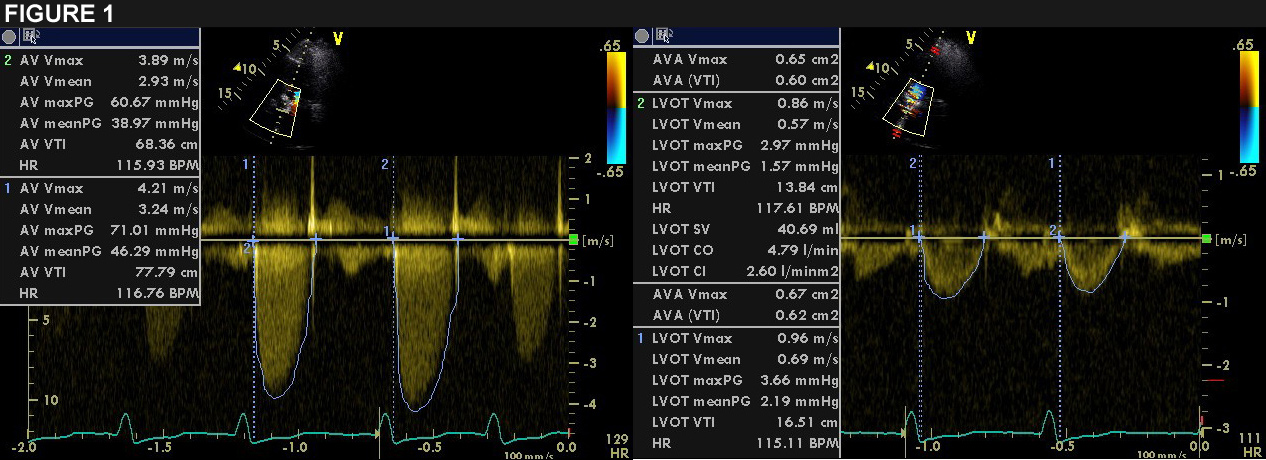

Echocardiography confirmed the severe stenosis of the aortic bioprosthesis with a maximum gradient of 66 mmHg, a mean of 43 mmHg and a valve opening area of 0.6 cm2 (Fig. 1).